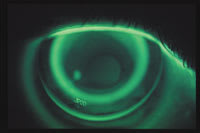

Figure 4: Photo of RG lens with shallow sag depth |

A Shallow Fit

Figures 3 and 4 show a poor fit. Note that in the diagram, the secondary zone does not make it to the cornea, leaving a gap. This failure creates a sag depth that is shallower than that of the cornea, which allows the lens to tilt and decenter. Figure 4 shows a high-riding lens with a very broad area of central touch, indicating a too-shallow sag depth and excessive pressure centrally. This will lead to induced astigmatism and "smiley-face" topography with a decentered treatment area. To fix the problem, have the lab increase the sag depth by steepening the secondary curve. It is important to note that the lenses have identical peripheral alignment. Changing the alignment curve will also affect the sag depth and the overall fit.